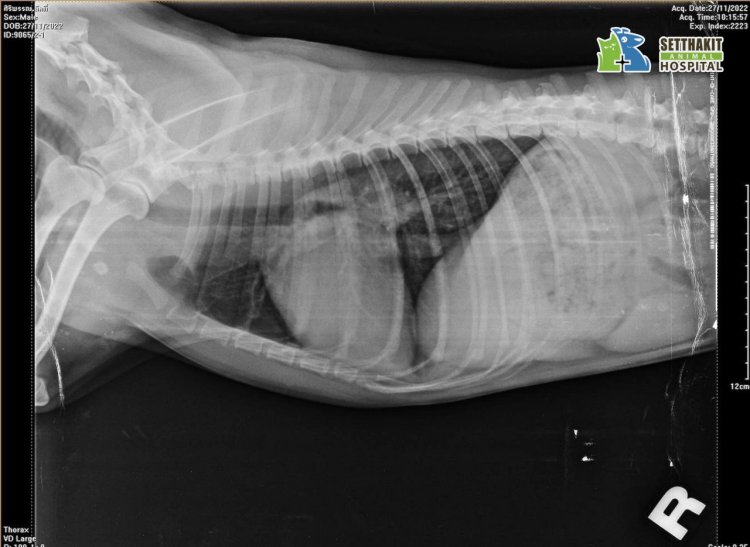

• X-ray imaging

ถ่ายภาพเอกซเรย์ช่องอก (X-ray)